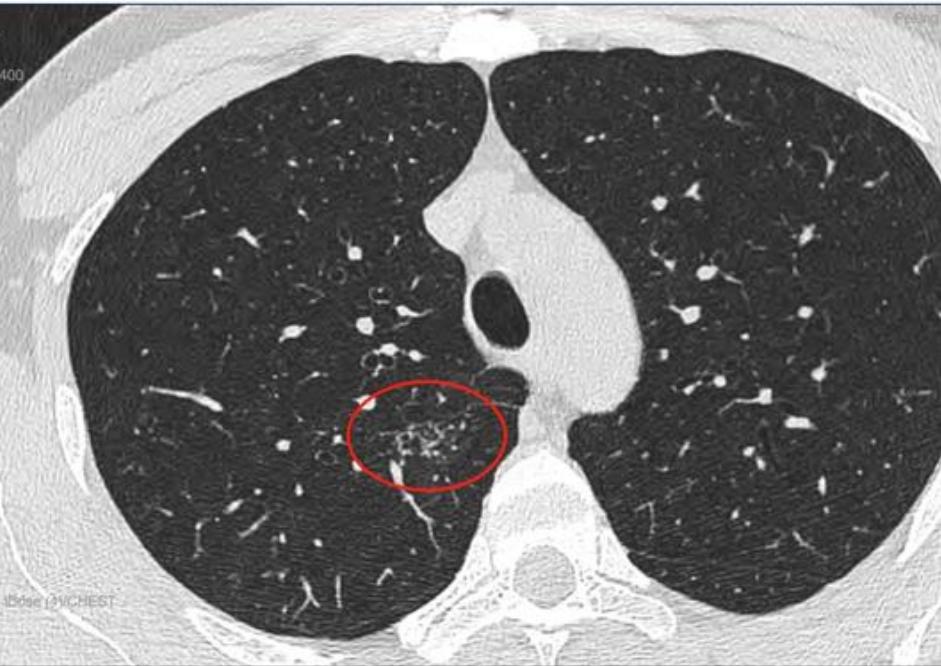

这是11月15日的CT图像与上次(7月29日)CT图像对比图:

再发一张:

辛苦主任,您看一下,结节虽然缩小了,还有1.7*0.9 CM,其他俩肺叶还有陈旧性病灶,应该继续服用拜复乐和夏枯草吗?8月份查过:男性肿标9项、过敏源检测(总IgE)、鳞状上皮细胞癌相关抗原、GM试验、隐球菌抗原、1,3-β-D葡聚糖 都是阴性,在正常范围内。就是结核感染T细胞还没查,您看是否需要查一下?主任辛苦您了,谢谢您!